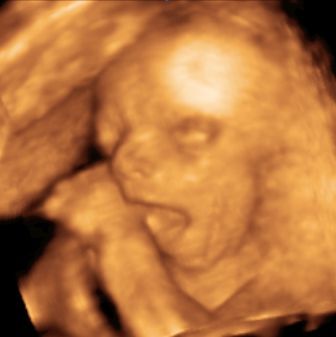

Gyorsan a lényeg!Úgy néz ki kislány!!!!!!

Mindjárt hozok képet is! :wink:

De akkor leírom az adatokat!

Napra pontosan akkora mint a vonalzóm!!!

671 g

BPD 6.12cm

FL 4.43 cm

AC 19.09.cm

Szerencsére nincs nagy feje :wink:

Ja és van egy kis bibi.Mindkét veséjében van vmi tágulat,de még nagyon pici.Egyenlőre nincs vele gond,de figyelni kell h nő e.Vkinek ezzel kapcsolatosan tapasztalat???

A név még nem dőlt el,holnap majd megbeszéljük apcimmal.A Mónika és az Izabel maradt versenyben!

Szerintem egyértelmű volt h lány,szépen oda lehetett látni.És bizony zacsi nem volt!Meg a csaj rávágta még a legelején h kislány!Pedig az csak 2D volt!!

Hát nekem is jobban tetszik az Izabel....de csak így,tehát nem Izabella.Ma el kell döntenem....az elején megegyeztünk h ha lány akkor én döntök...de apcimnak is nagyon tetszik a kis Izi